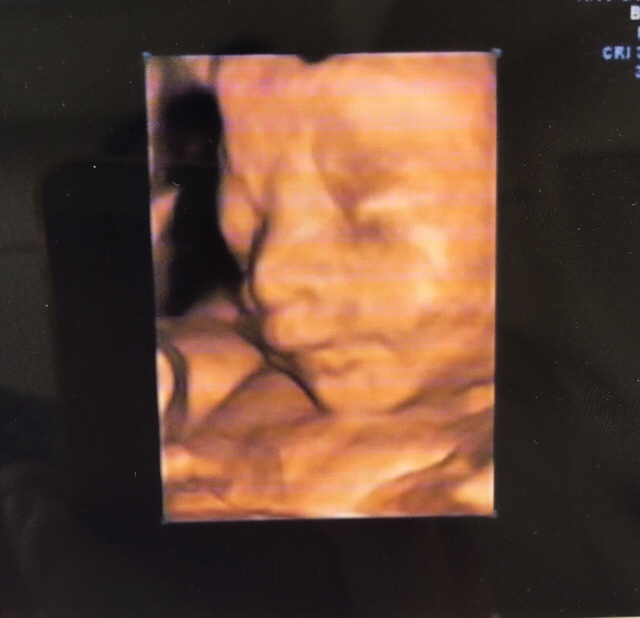

孕25周+5天

鼻子好挺,漂亮